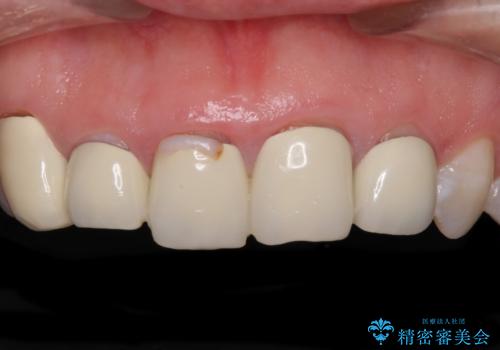

- 歯列不正を改善する目的で装着した前歯のセラミックが気になるとのことで来院された患者様です。

金属の裏打ちを用いたセラミッククラウンであったため歯肉縁に黒ずみが見えてくることは良くありますが、全体的に歯列が不揃いであることが気になったので、それらをオールセラミッククラウンにて改善することとしました。

セラミッククラウンが外れてしまうことを心配して、歯ブラシをあまり当てられなかったとのことで、歯肉に軽度の炎症が認められました。